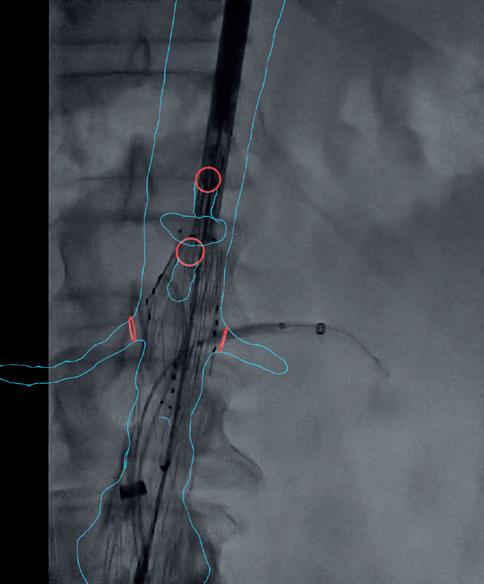

Just recently, Cydar added Last Verified Map (Figure 1). This tool helps with vasculature visibility when there is not enough observable anatomy for image tracking. This kind of improvement as well as swift alterations are characteristic of software-built solutions.

Figure 1. Last Verified Map is displayed on the digital subtraction angiography (DSA) image as the vertebral anatomy has been subtracted